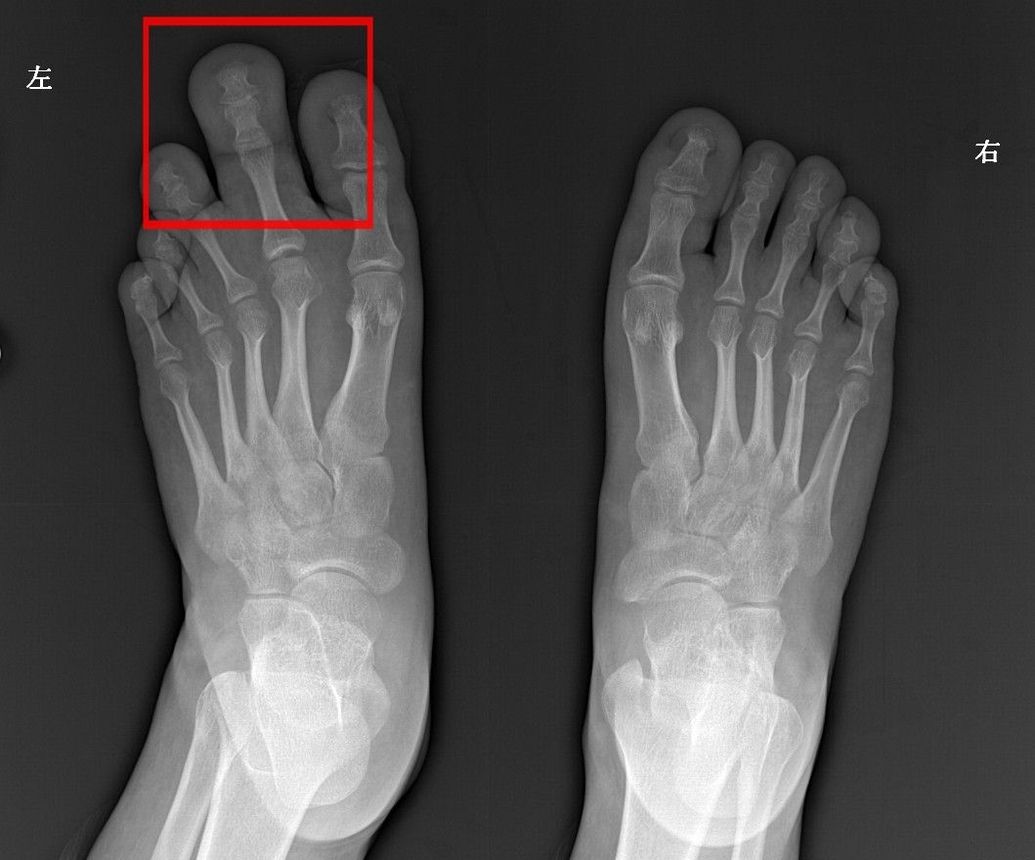

中山男子20年没有合穿的鞋子,原因很罕见

踇外翻——对女性造成困扰最大的足部畸形_刘津浩医生

濮阳三院骨科——给我一双美丽的脚